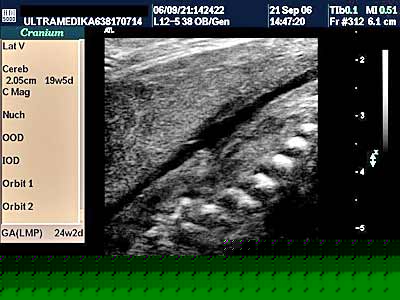

Ultrazvučna dijagnostika lokalizacije spine bifide i korelacija sa posledicama nakon rođenja

Mielomeningokela (omotač i kićmena moždina van tela ploda) u zavisnosti od obima nerazvijenosti kičme se rangiraju od malog do velikog defekta a nazivaju se defekt neuralne cevi (NTD).

Još davne 1990 godine postavljeni su ključni ultrazvučni markeri kao što su znak limuna (izmenjen izgled lobanjskih kostiju) i spina bifida -SB(izmenjene koštane strukture kičme ploda).

Osim ovih markera visina lezije na kičmenom stubu i veličina komornog sistema mozga (ventrikulomegalija) predstavljaju dodatne markere koji daju prognozu za ovakve plodove nakon radjanja.

Uobičajeno mišljenje je da nisko položen defekt kičme i manji porast komora mozga znače bolju prognozu , nego više položena SB i izraženija ventrikulomegalija. Odatle sonografsko odredjivanje visine SB i njenog tipa čine osnovu za predvidjanje prognoze stanja ploda nakon radjanja.

Da bi UZ dijagnostika bila senzitivna 100%, mora se znati da kod niskih lezija mogu izostati UZ markeri u glavi ploda( ne postoji znak “banae” i “limuna” i td), te je obavezan pregled kompletnog kičmenog stuba.

Ovaj pregled često nije adekvatno sproveden jer su obavezni sagitalni, transverzalni i aksijalni preseci kompletne kičme. Često ovo nije moguće uvek uraditi zbog konsistucije trudnice i položaja kičme. Multiplanarna analiza sve tri ravni kod 3D obrade volumena može u jednom procentu biti od pomoći. Osnova uspešnog pregleda je absolutni insistiranje na sprovodjenju kompletnog ultrazvučnog protokola kod pregleda kičmenog stuba ploda.